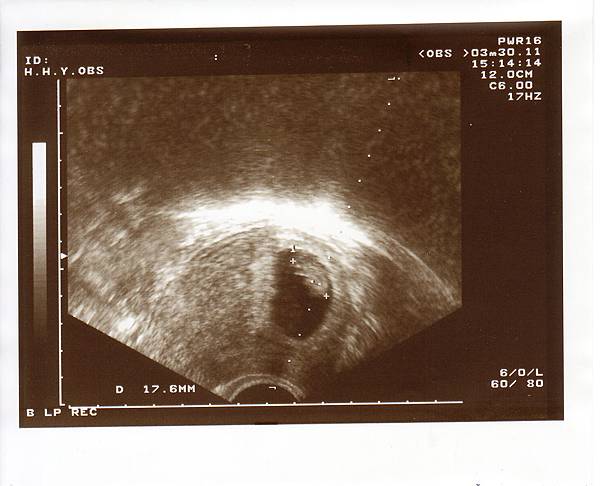

2011.03.30 終於比較清楚地看到小寶寶